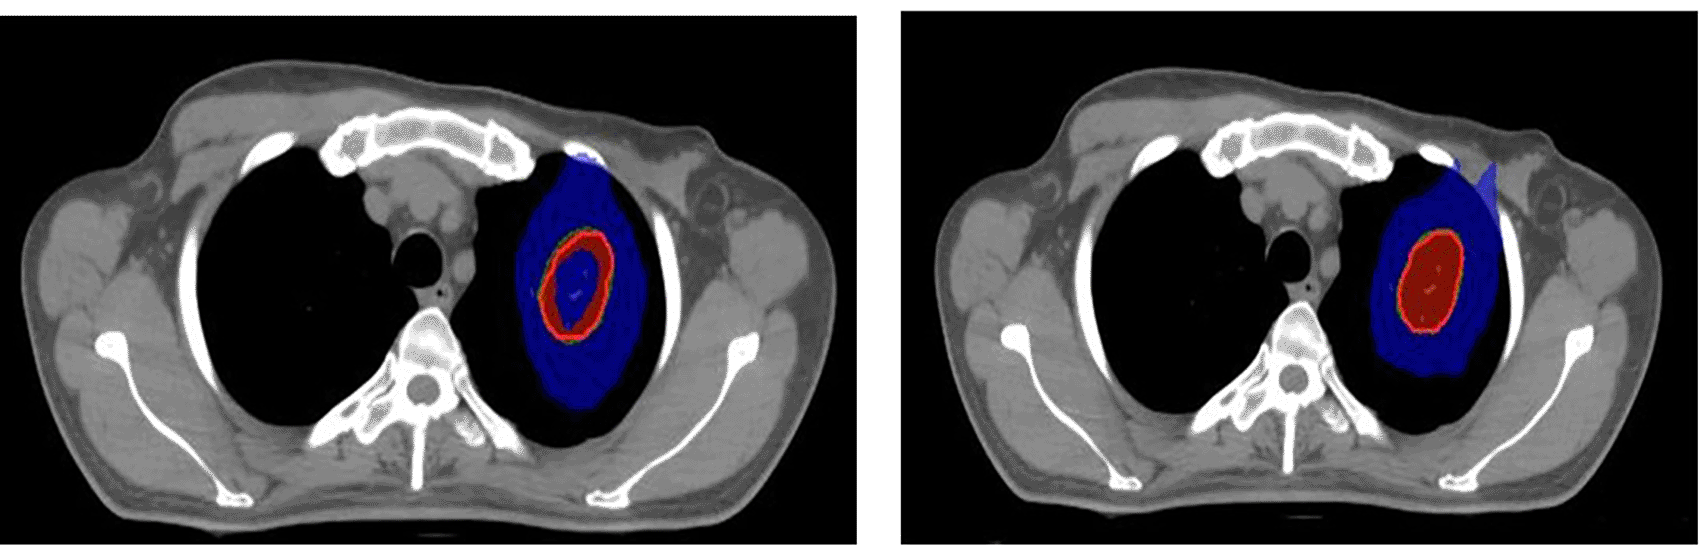

The first plan for SRS/SBRT was developed using the dynamic conformal arc therapy (DCAT) technique with a 6FFF photon beam energy using a 2.5 mm Apex mMLC. The Apex mMLC is an additional attachment to the collimator of the Elekta Versa high-definition LINAC consisting of an MLC with a 2.5 mm width at the isocenter. This high-resolution collimating device is especially used for SRS treatment delivery to facilitate conformal dose distribution around the tumor. The maximum field size provided by the mMLC is 12 × 14 cm2.25 The isocenter was placed at the center of the target volume. The number and direction of the arcs were chosen based on the location of the tumor. Couch movement was restricted in some cases, wherever it was practically impossible to move the gantry with the Apex to reduce the risk of collision of the gantry with the couch and patient. The second plan was generated without using Apex mMLC. The LINAC has an inbuilt MLC with a 5 mm width at the isocenter, which is also called Agility. The SRS/SBRT treatment plans in this case were performed with agility using a 6FFF photon beam energy. The treatment plan was implemented using the same gantry couch combinations. Multiple optimizations in both techniques were performed to achieve the prescribed tumor dose and to bring the dose to the OARs within the given limits. The Monte Carlo algorithm was used to calculate the dose distribution.26 For the included cases, SRS was planned with 16 Gy in one fraction (Figure 1) and SBRT with 60 Gy in five fractions (Figure 2).

Red: 100% prescribed dose; Green: 95% prescribed dose; Blue: 50% prescribed dose; Yellow: 115% prescribed dose.